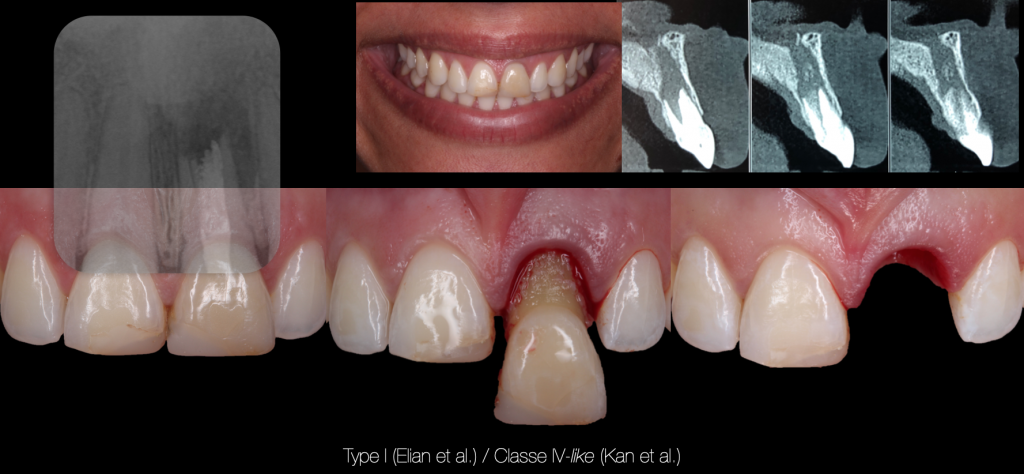

However, bone resorption is predominantly in the vestibular coronary third (Chappuis et al., 2013). Januario et al. (2011) show that the bony bone table in the anterior maxillary area is thin (0.6 mm on average and less than 0.5 mm in more than one case out of two) and that the more the cortical bone is thin, the more its resorption is important.

Clinical Case